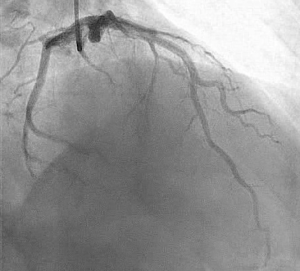

The patient was admitted to the cardiovascular intensive care unit and extubated the same day, neurologically intact. An urgent left heart catheterization revealed diffuse mild coronary atherosclerosis with normal ejection fraction. He was transferred out of the intensive care unit the next day and discharged shortly after, neurologically intact and at baseline.